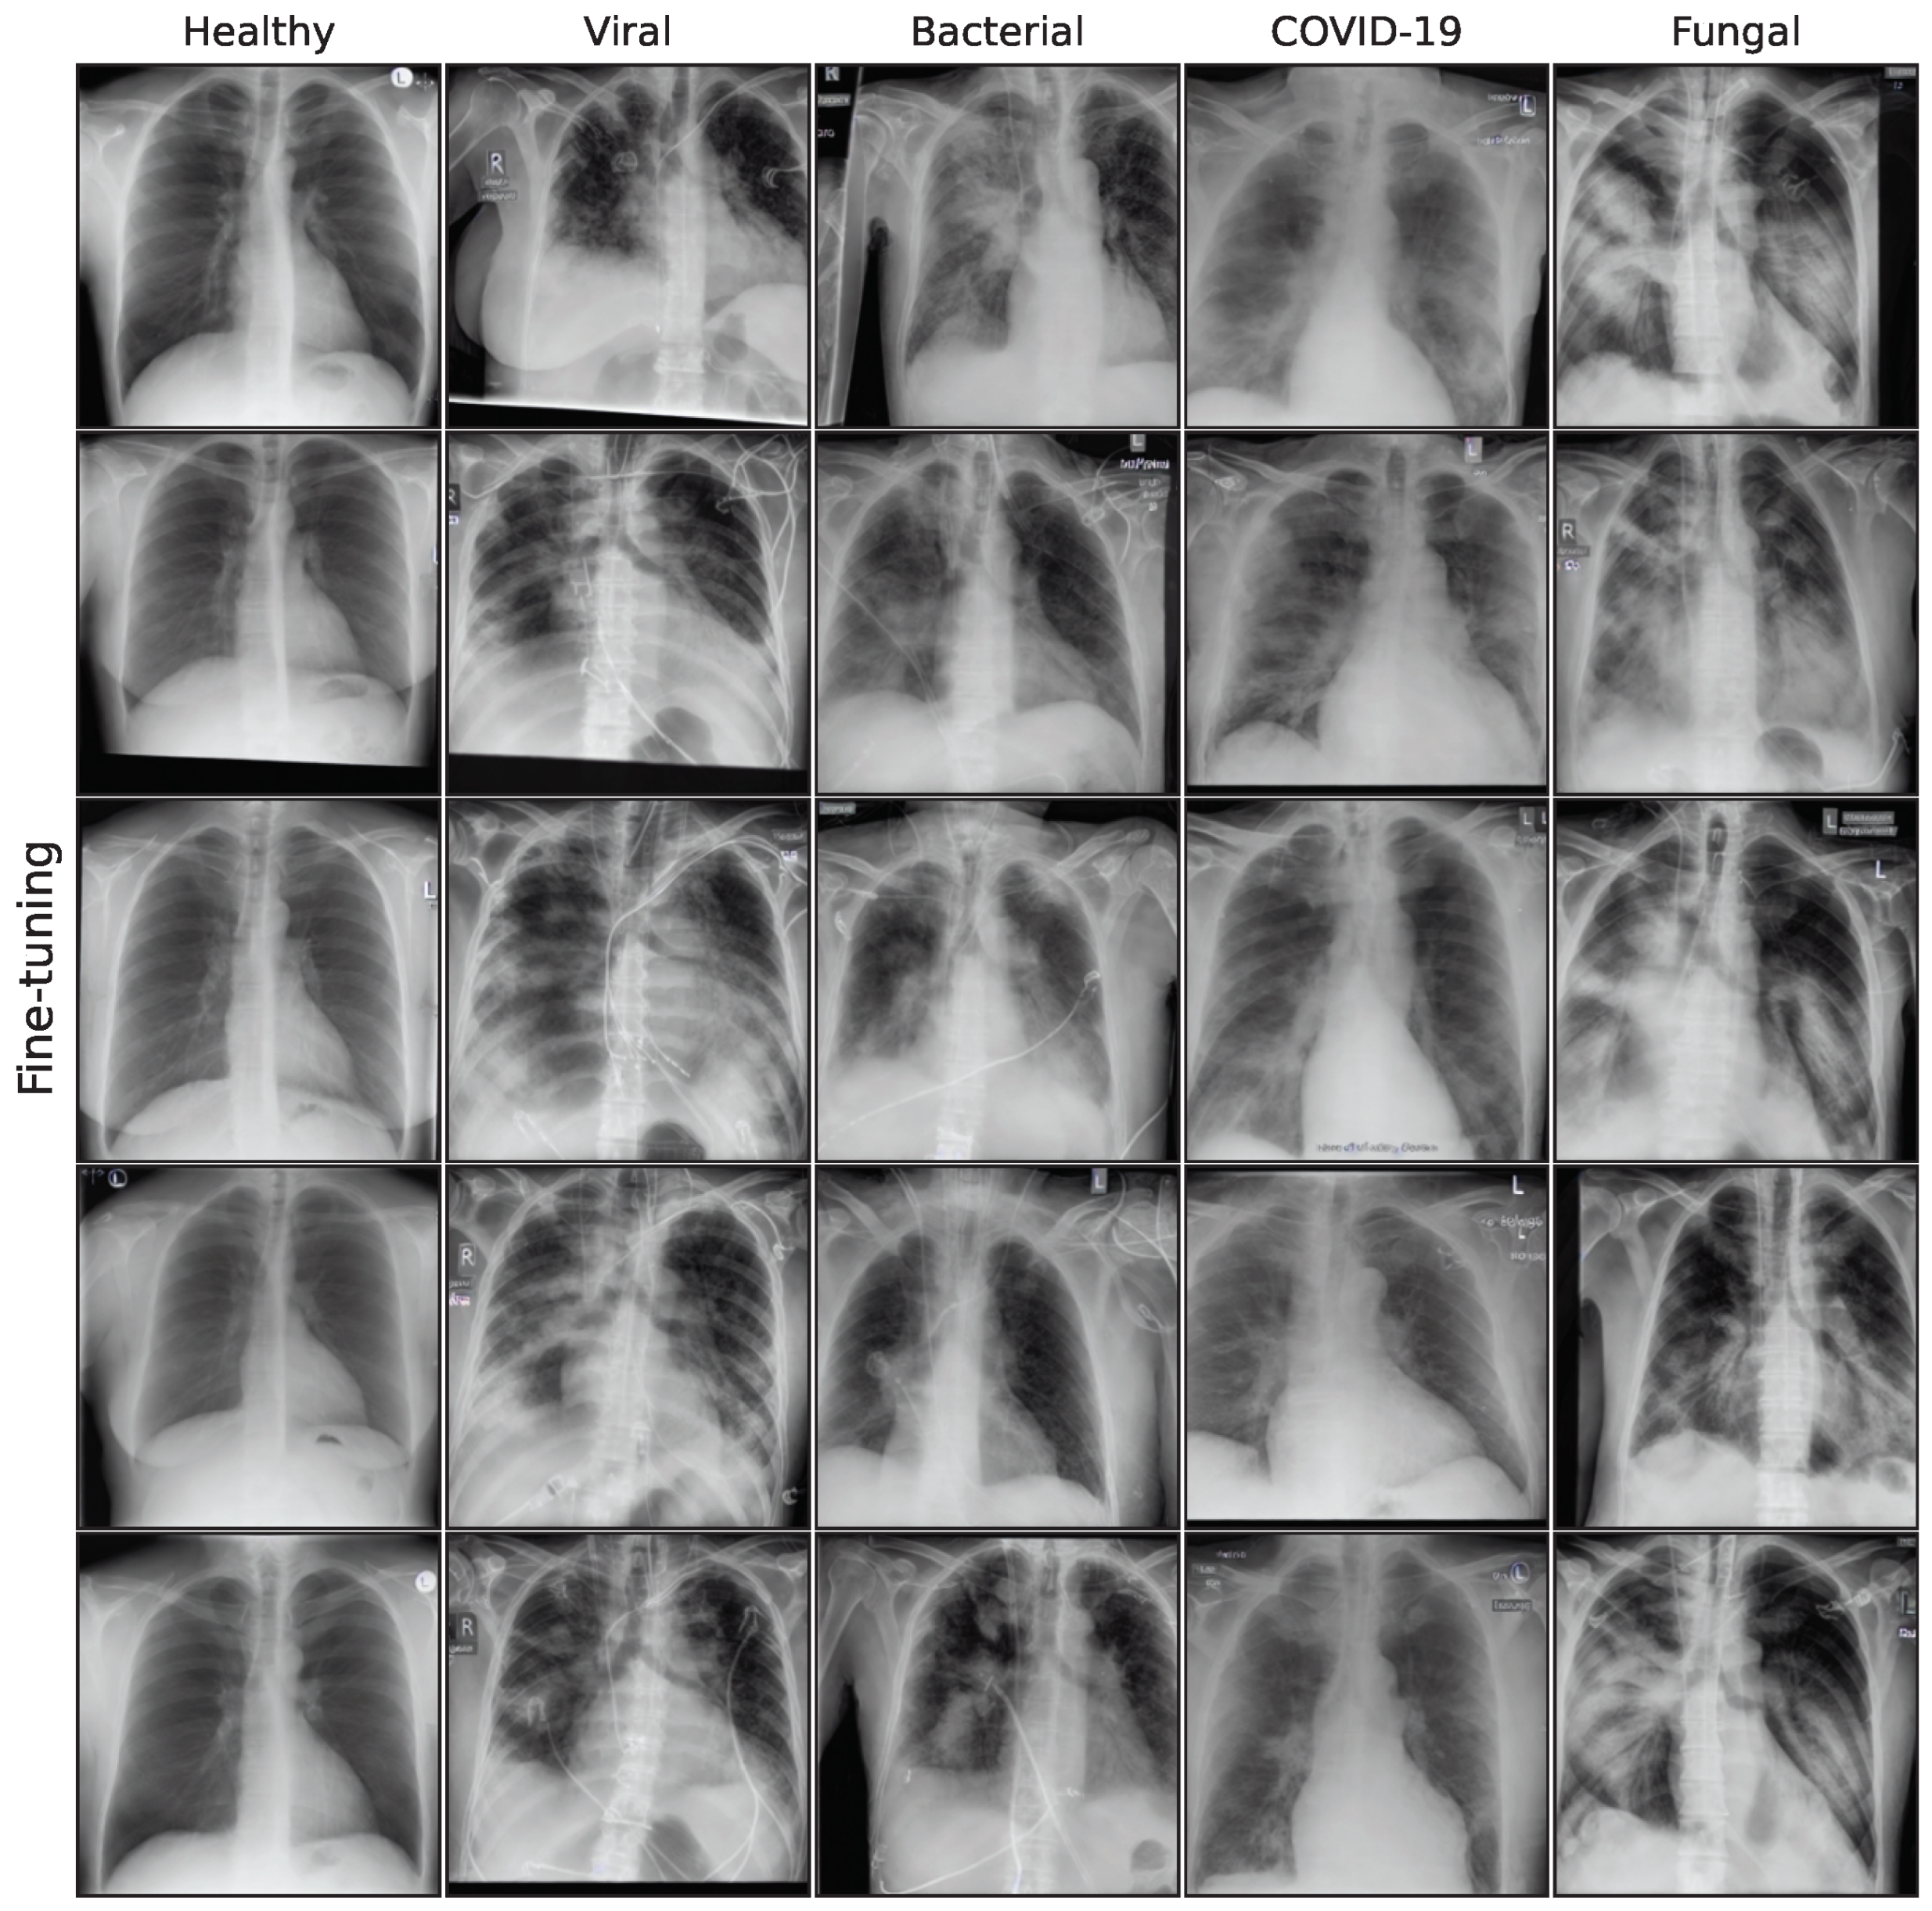

The dataset of this study was initially described in Schaudt et al. [14] and contains 1082 chest X-ray images from a total of 828 patients (342 female and 486 male) with ages ranging from 18 to 89 years (mean age 52.52 ± 17.45 years). Radiographs were acquired during chest radiography examinations due to clinical symptoms on a portable flat detector (Flurospot Compact Siemens Healthcare, Erlangen Germany and DRX Evolution Carestream, Stuttgart, Germany). The ethics board of the Medical Faculty and the University Hospital in Ulm approved this retrospective data evaluation study and waived the informed consent requirement (No. 271/20). All methods were carried out in accordance with relevant guidelines and regulations. Figure A1 in the Appendix A shows a sample collection of 5 images per class.

3.2. Image Synthesis

Figure A1. Sample images from original dataset.

Bioengineering 10 01421 g0a1